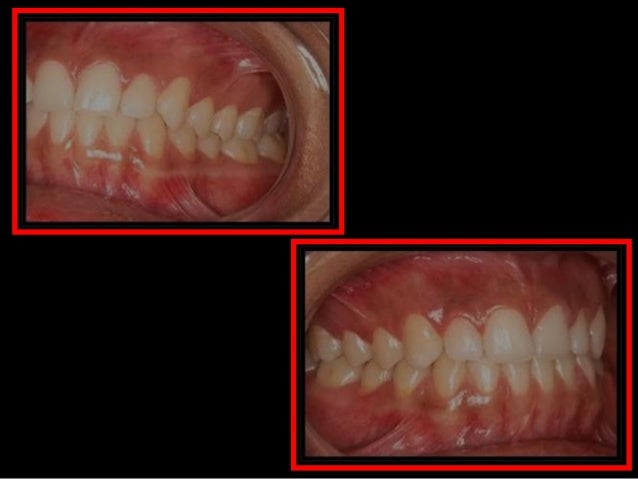

21. 21. Classe I -Normoclusão

22. 22. Classe II- Maxila avança a Mandíbula

23. 23. Classe III-Mandíbula a frente da Maxila

24. 24. Mordida Cruzada- Mandíbula cobre parte da Maxila